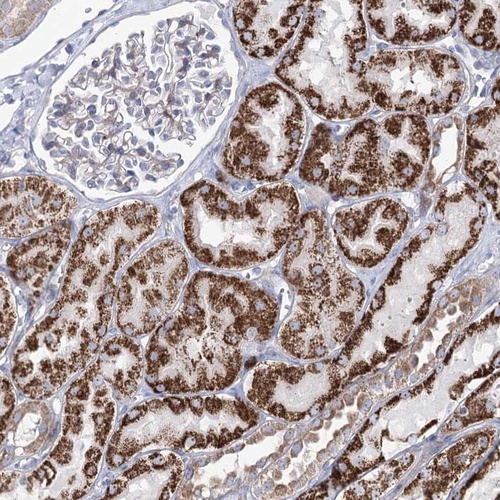

Immunohistochemical staining of human kidney shows strong cytoplasmic positivity in cells in tubules.